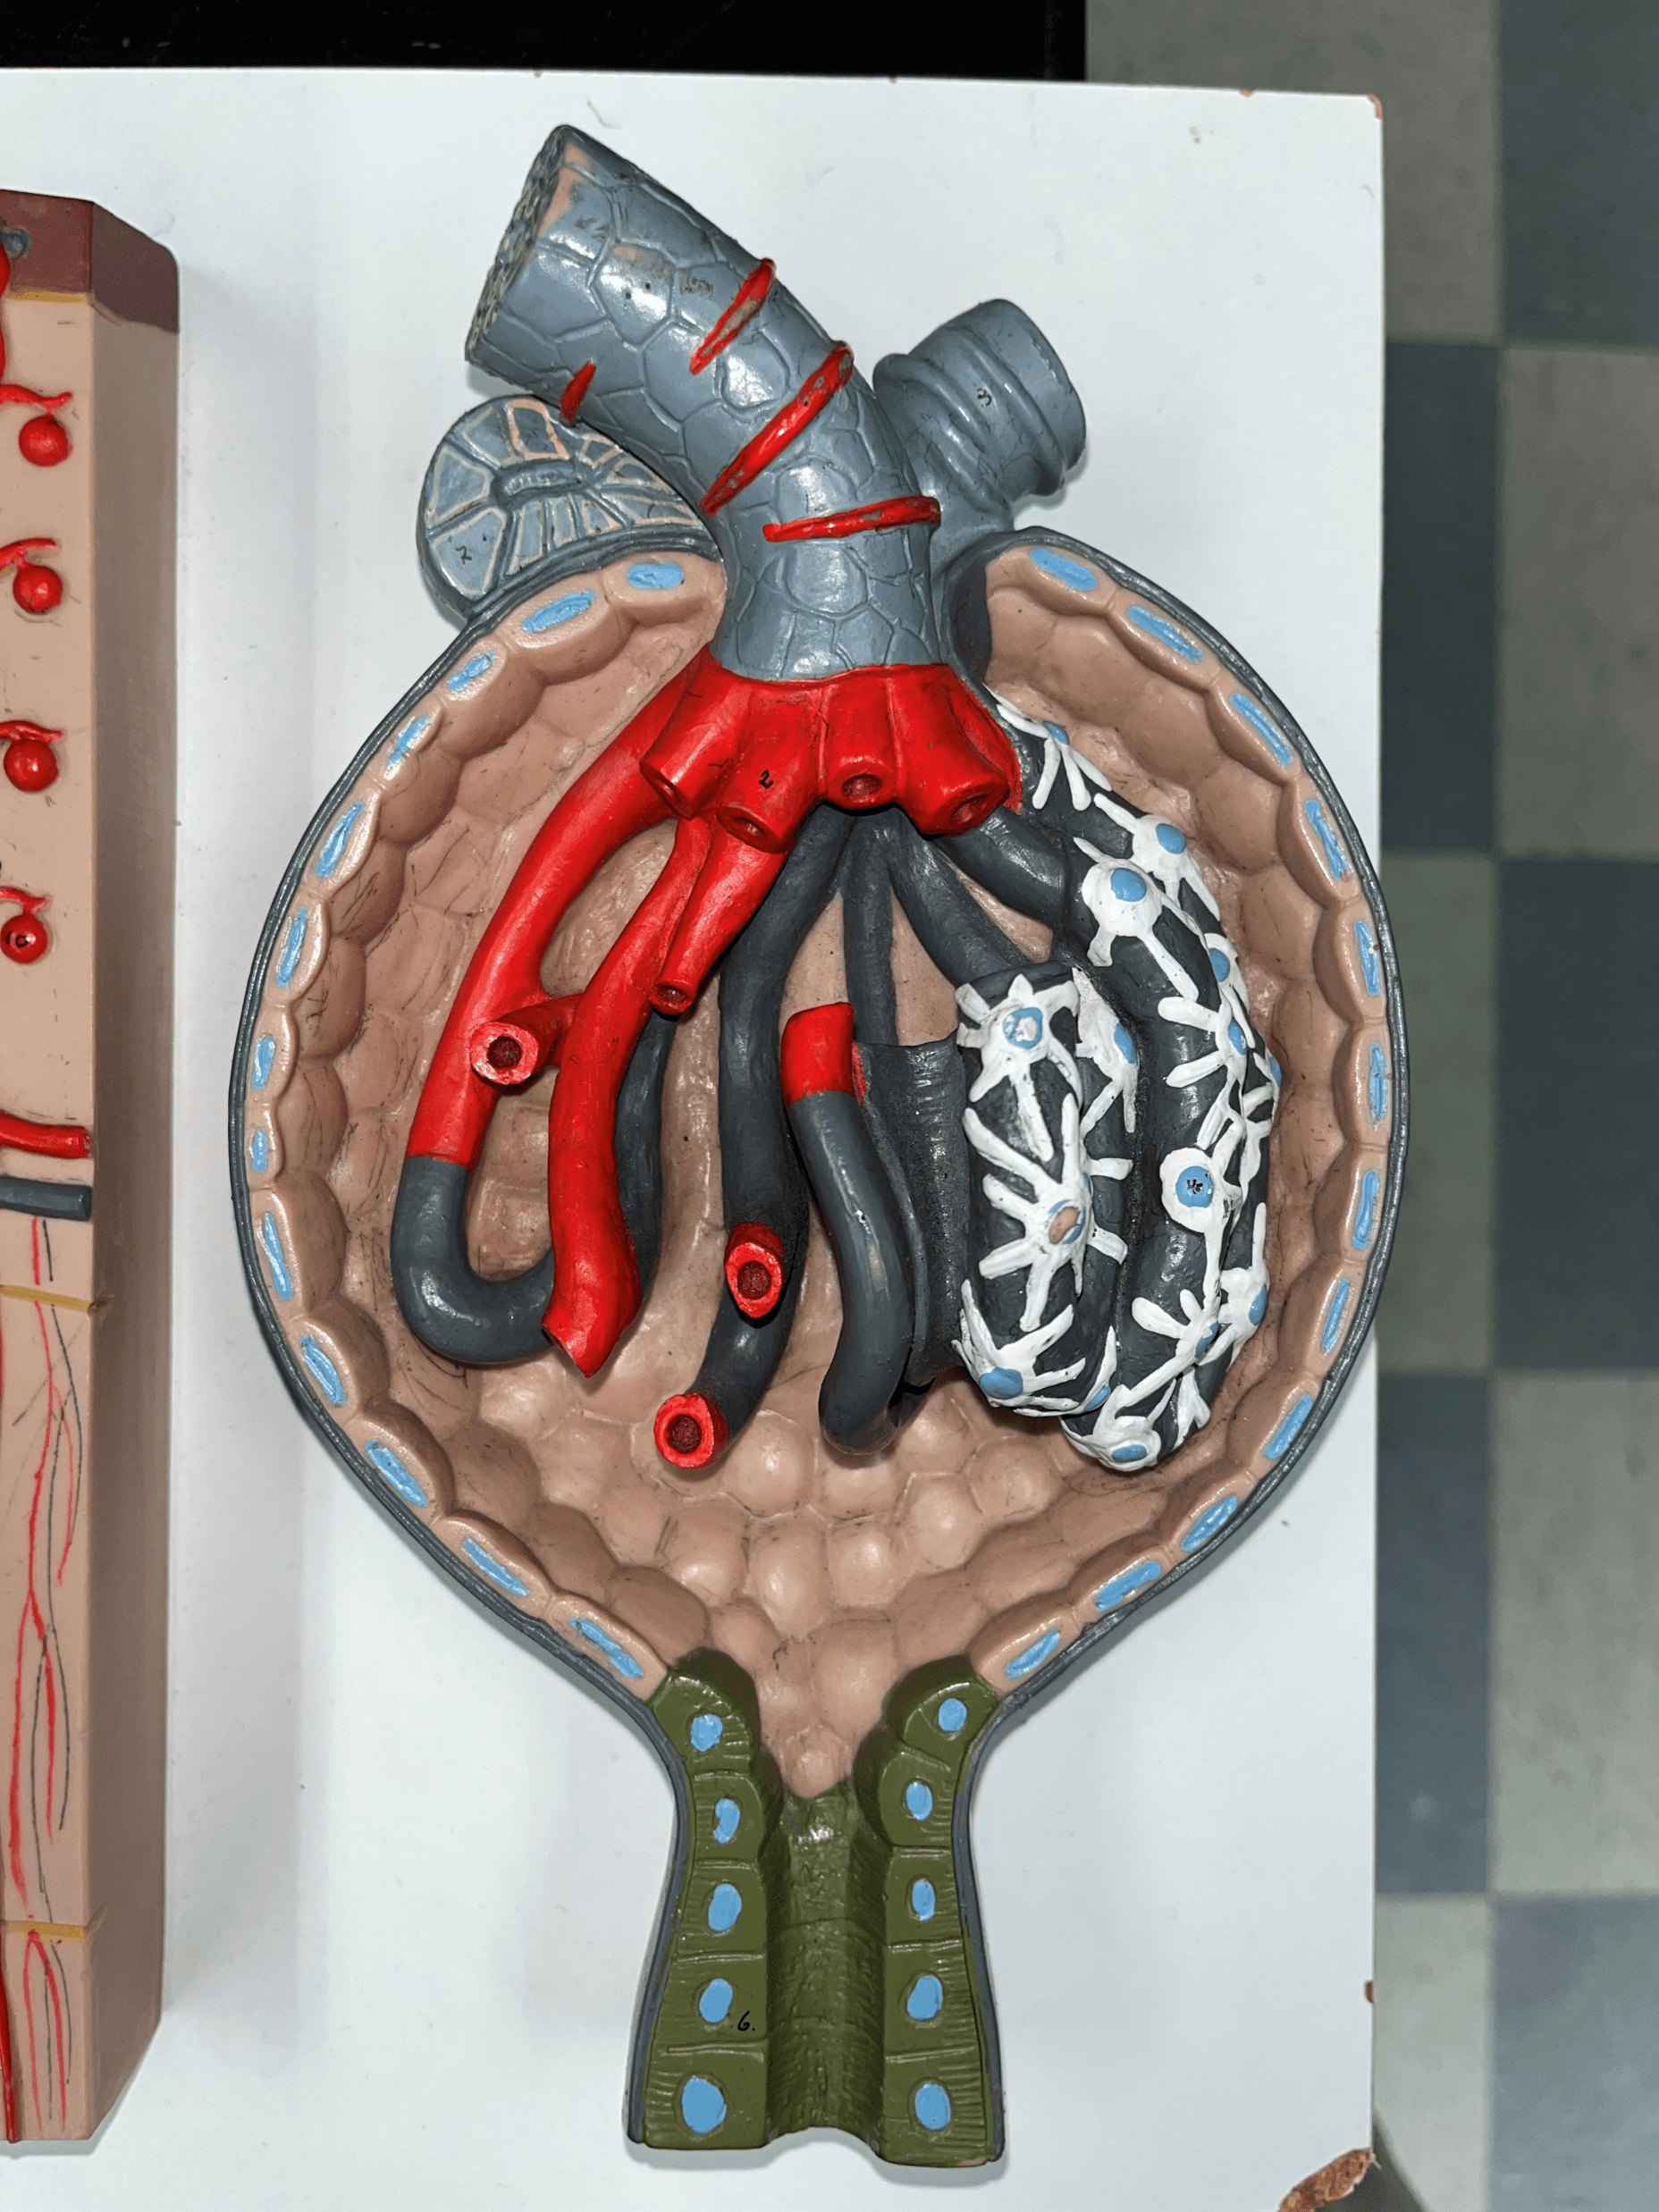

kidney

The organ that filters blood and excretes waste as urine.

renal capsule

The thin outer shell of the kidney.

renal hilum

• The concavity of the kidney.

• Admits the ureters, renal a., renal v., lymphatics, and nerves.

• Also known as the hilus of the kidney.

renal cortex

• The outermost region of the internal kidney.

• Superficial to the renal medulla.

• Appears slightly granular.

renal medulla

• The middlemost region of the internal kidney.

• Deep to the renal cortex and superficial to the renal pelvis.

• Contains triangular renal pyramids.

• Appears striated due to the presence of tubules and ducts.

renal pyramid

• A triangular structure found in the renal medulla.

• The base faces the renal cortex.

• The renal papilla (apex) faces the renal pelvis.

• The renal papilla (apex) faces the renal pelvis.

minor calyx

• A cup-like extension that collect urine from the renal papilla.

• Converges with others to form a larger major calyx.

major calyx

• The convergence of several minor calyces.

• Drains into the renal pelvis.

renal pelvis

• The innermost region of the internal kidney.

• Collects urine from the major calyces and drains it into the ureters.

• Includes the minor and major calyces.

renal artery

• The largest a. of the kidney.

• Supplies the entire kidney.

• Branches into smaller segmental aa.

segmental artery

• Branches of the renal a.

• Branches into smaller interlobar aa.

interlobar artery

• Extends between the renal pyramids.

• Branches of a segmental a.

• Branches into smaller arcuate aa.

arcuate artery

• Extends along the base of the renal pyramids.

• Branches of an interlobar a.

• Branches into smaller interlobular aa.

interlobular artery

• Extends through the renal cortex.

• Branches of an arcuate a.

• Branches into an afferent arteriole of a glomerulus.

interlobular vein

• Extends through the renal cortex.

• Converges into an arcuate v.

arcuate vein

• Extends along the base of the renal pyramids.

• The convergence of interlobular vv.

• Converges into an interlobar v.

interlobar vein

• Extends between the renal pyramids.

• The convergence of arcuate vv.

• Converges into the renal vein.

renal vein

• The largest vein of the kidney.

• Drains blood from the entire kidney.

• The convergence of interlobar vv.

ureter

• A narrow tube channeling urine from the kidneys to the urinary bladder.

• Composed of an outer adventitia, middle muscularis, and inner mucosa.